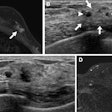

The sonographic images were of the right upper quadrant, subxiphoid, left upper quadrant, bladder, aorta, and right lung, as well as right internal jugular vein views to verify central line insertion.

A total of 189 images were obtained from 27 exams. The images were evaluated by two blinded emergency sonographers who were certified in ultrasound image interpretation, along with a board-certified radiologist. Each was asked to assess and rank both image quality and clinical utility on a scale of 1 to 10.

Session presenter Dr. Davut Savaser, an attending ED physician and a clinical instructor in emergency medicine, said that all 189 images received a score of 8 or higher by all reviewers. The hand sanitizer scored the best, at a median of 9.2, followed by the hairstyling gel and olive oil at 8.9. The images acquired with ultrasound gel were rated at 9.6.